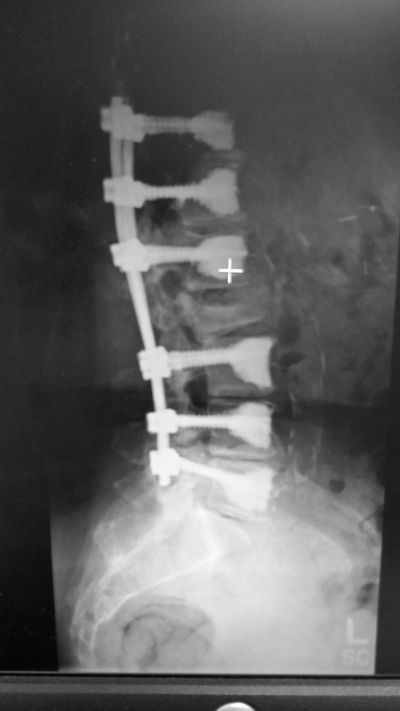

Dr. Morreale invented and pioneered the spine surgical procedure called Kyphofusion (also known as Kyfusion). This surgery can be done by way of either a traditional approach or a minimally invasive one. It is used for patients who would not be able to have surgery including elderly patients, patients with poor bone quality and cancer patients.